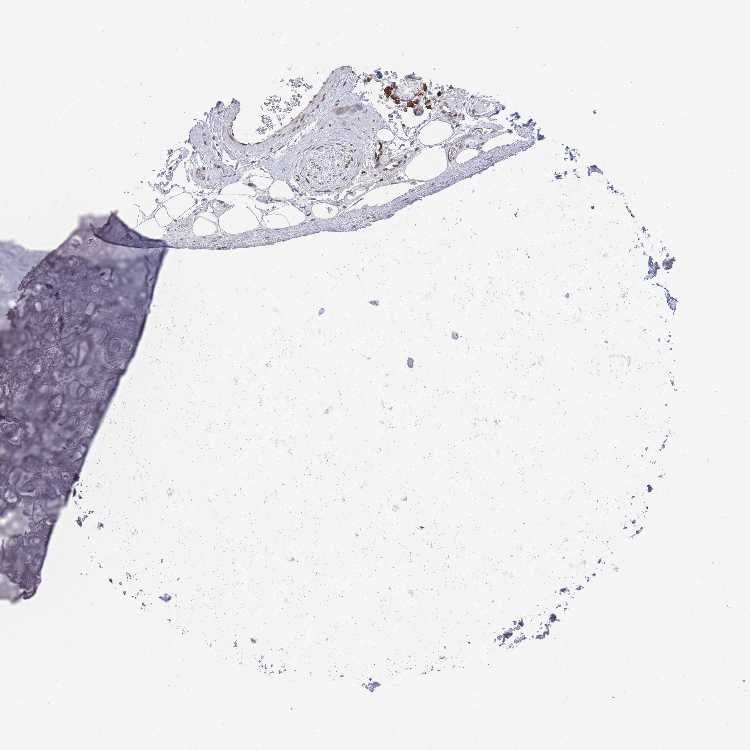

SOFT TISSUE 1 - Antibody stainingi

Antibody staining in the annotated cell types in the current human tissue is reported as not detected, low, medium, or high, based on conventional immunohistochemistry profiling in selected tissues. This score is based on the combination of the staining intensity and fraction of stained cells.

Each image is clickable and will lead to virtual microscopy that enables deeper exploration of all samples and also displays staining intensity scores, fraction scores and subcellular localization as well as patient and tissue information for each sample.

Antibody HPA050516

Chondrocytes Not detected

Fibroblasts Not detected

Peripheral nerve Not detected